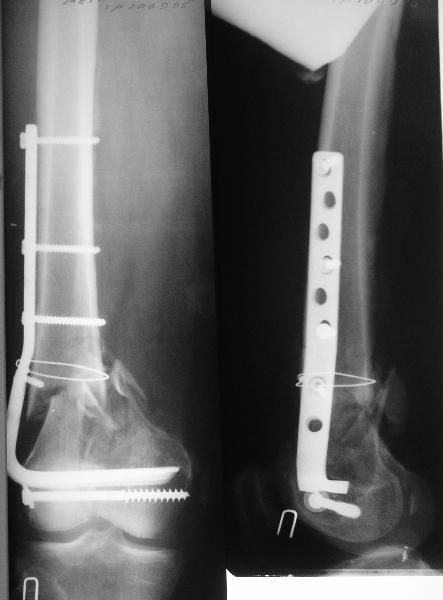

Мужчина 60 лет, оперирован 2 месяца назад в другом регионе. На сегодня

вот такая картина. Укорочение около 2 см. Движения в колене - 45

градусов.

Наверно, надо удалить эту пластинку и сделать реостеосинтез. Хочется

гвоздем. Или лучше не гвоздем? Как быть с укорочением? Как устранять

смещение? Надо ли что-то одномоментно делать по поводу контрактуры

колена? Спасибо!